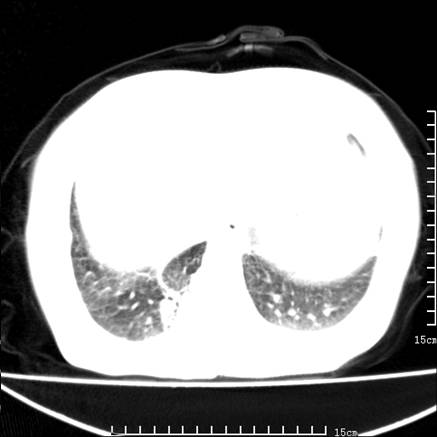

女,王某,58岁,咳嗽三个月余,基层医院二个月前诊为肺结核,用抗结核药二个月无明显疗效。

心包积液致肺瘀血.右侧周围型肺癌伴肺内转移,中间裂积液,叶间胸膜肥厚.右上肺大泡,右侧胸膜肥厚.

双肺继发型tb,心功能不全并肺淤血、心包、双侧叶间裂积液,肺大泡,右下胸膜肥厚钙化。

支持  双肺继发型tb,心功能不全并肺淤血、心包、双侧叶间裂积液,肺大泡,右下胸膜肥厚钙化。